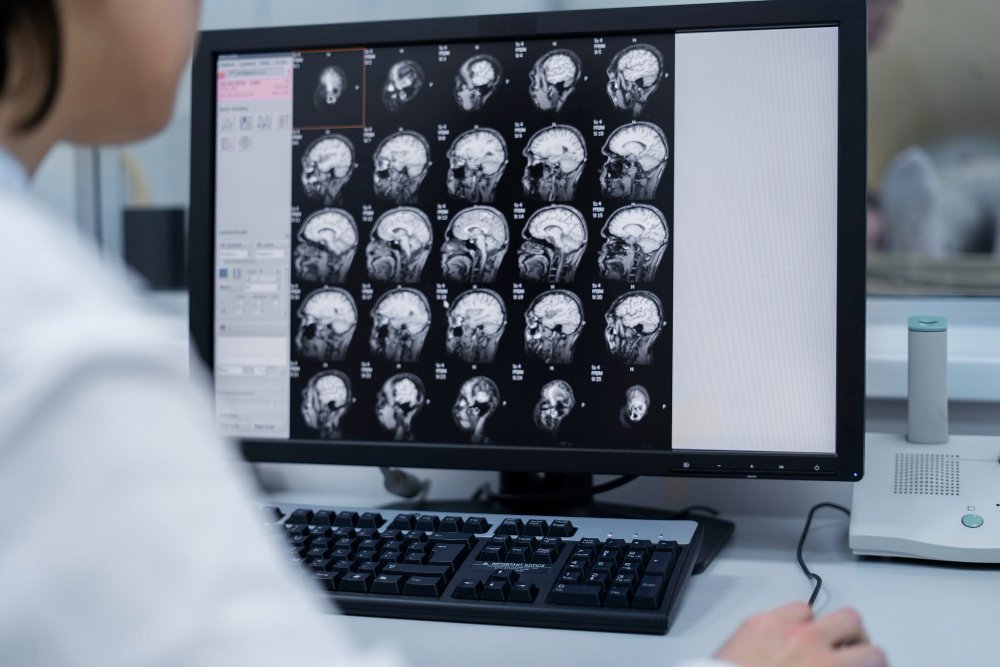

An upright MRI is a modern imaging solution that allows patients to be scanned while sitting, standing, or in a partially reclined position. Unlike traditional MRI machines that require patients to lie flat in an enclosed space, the upright design offers greater comfort and flexibility. This innovative technology provides clear, high-quality images of the body, especially for conditions that worsen when a person is upright or in motion.

The upright position allows specialists to observe how gravity and posture may affect blood flow and brain pressure, improving diagnostic accuracy.

Yes, an Upright MRI produces high-quality images, especially for spine, posture, and joint conditions that require scanning in weight-bearing positions.